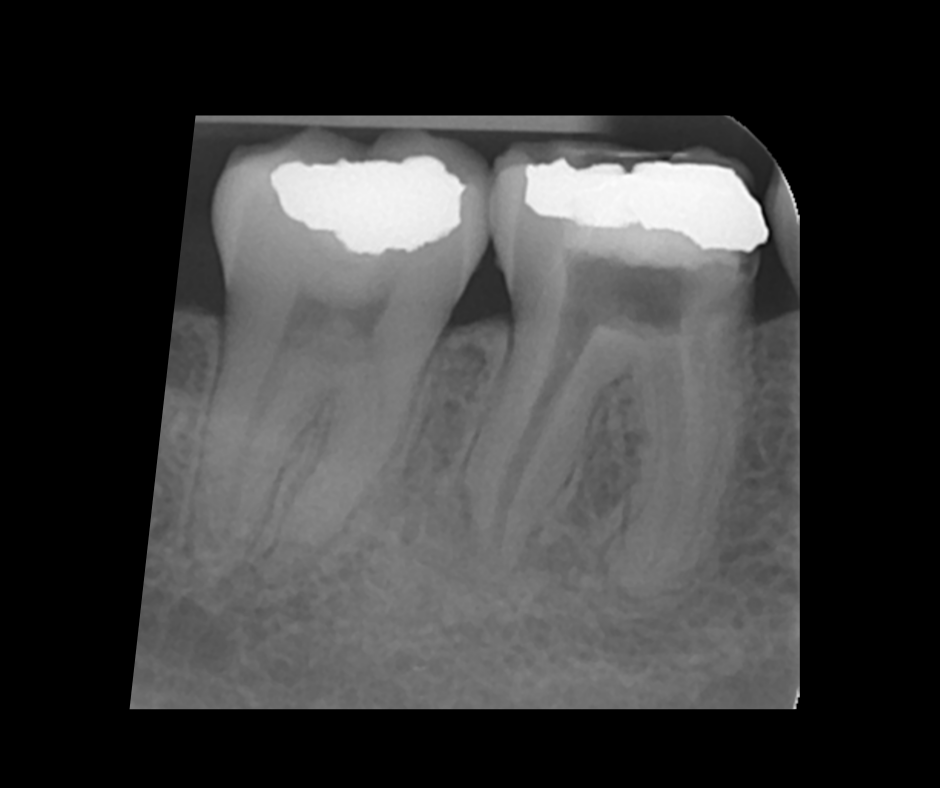

This course focuses on modern single-file endodontic systems, guiding participants through diagnosis, case assessment, access cavity design, canal location, root canal system preparation, and obturation techniques.

• To gain confidence in endodontic obturation and develop an understanding of various obturation techniques and methods of developing predictable, reproducible endodontic obturation